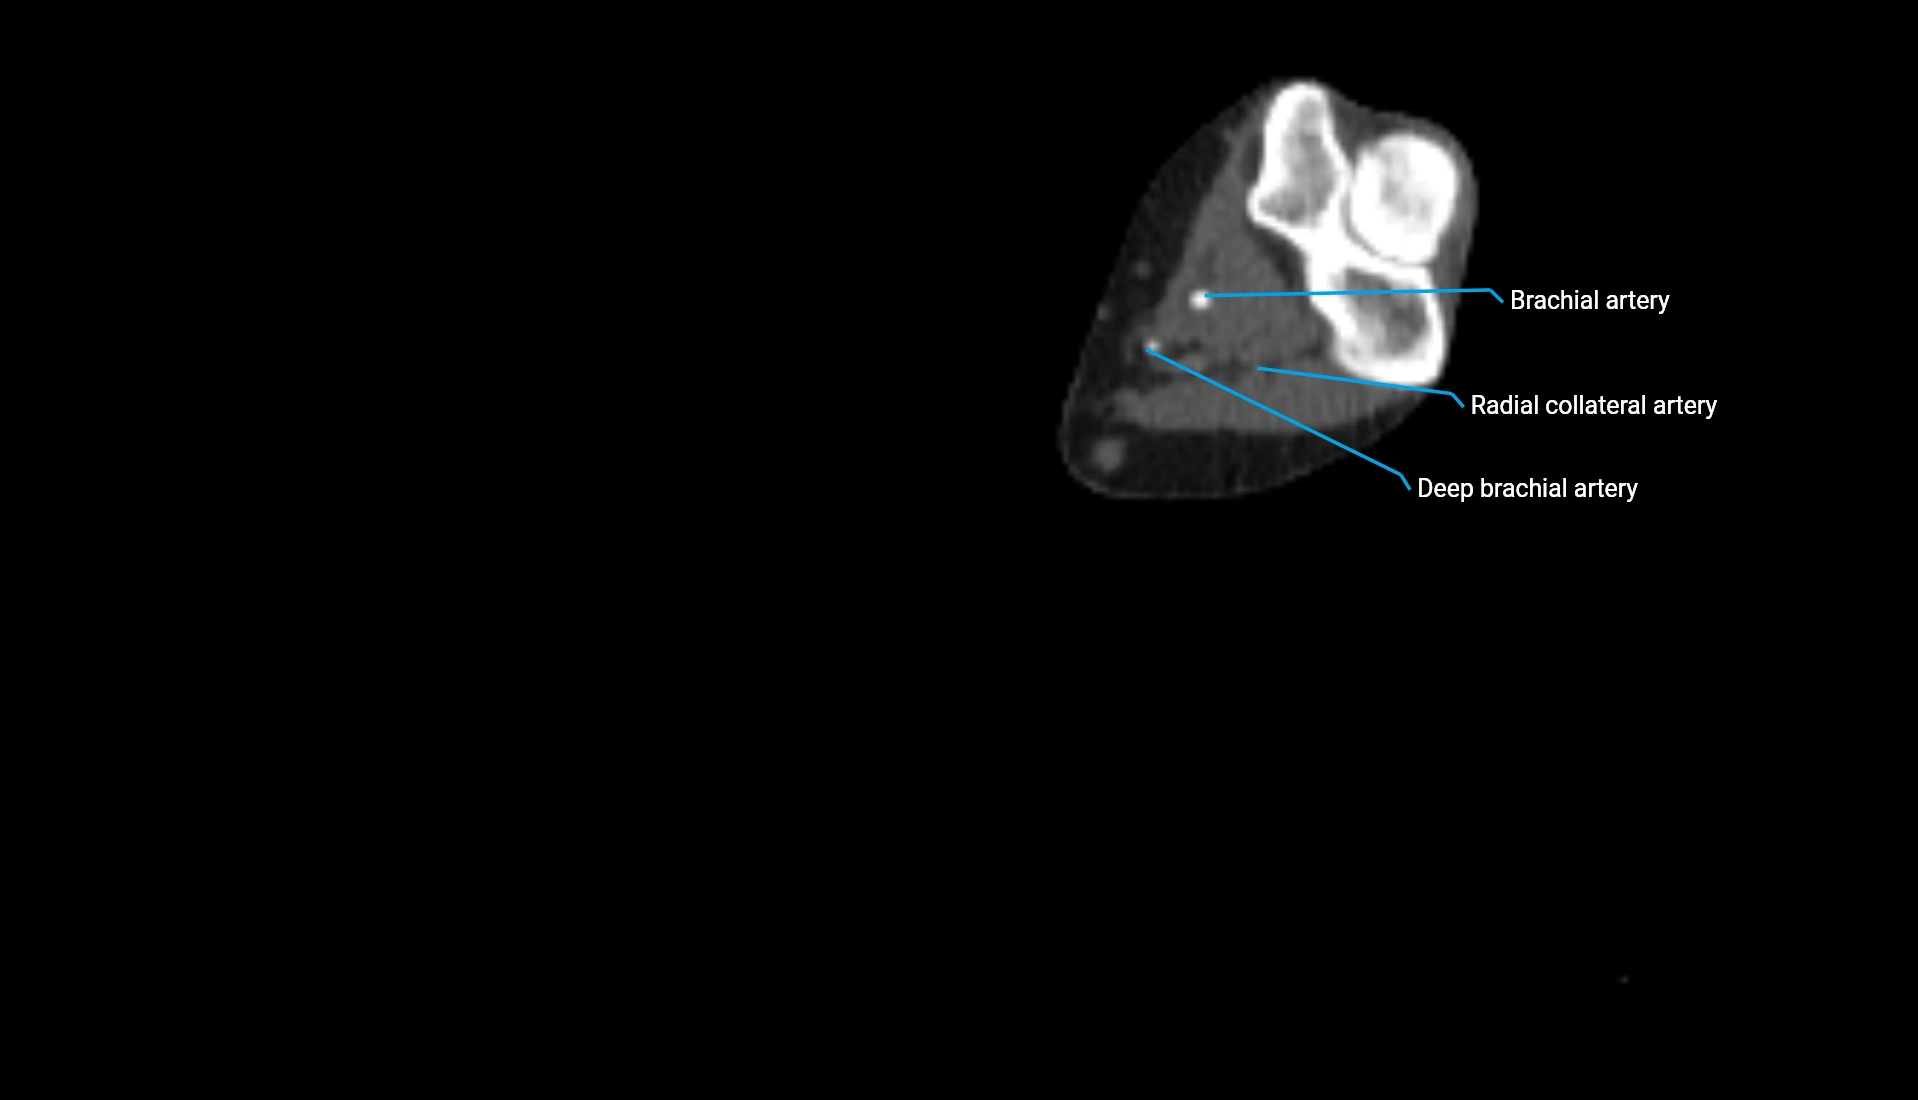

CT Appearance

Non-Contrast CT:

• Cortex: High-density, sharply defined

• Subchondral bone: Dense cancellous matrix

• Articular surface: Smooth concave contour articulating with the capitellum

• Excellent for evaluating bone integrity, alignment, and subtle fractures

Post-Contrast CT:

• Bone: No enhancement

• Joint capsule and synovium: Mild enhancement outlining the joint

• Improves contrast between soft tissues and bony margins

• Useful in detecting subtle joint abnormalities or postoperative changes